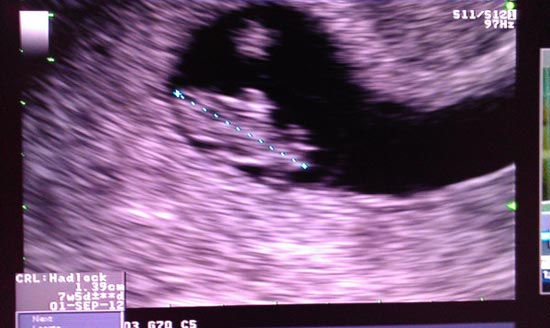

ล่าสุด คนที่คอยลุ้นทั้งคู่อยู่ ก็ขอให้ร้องเฮกันดัง ๆ ได้เลย เมื่อหนุ่มแบงค์ ได้ประกาศผ่านทวิตเตอร์ส่วนตั วของเขาพร้อมภาพอัลตร้าซาวด์ ประกอบว่า ภรรยาของเขาตั้งครรภ์ได้ 7 สัปดาห์แล้ว งานนี้ กระปุกดอทคอม ก็ต้องขอแสดงความยินดีกับว่าที่ คุณพ่อแบงค์และว่าที่คุณแม่นิ หน่าด้วยนะค้า ขอให้ทั้งคุณแม่และคุณลูกสุ ขภาพแข็งแรงและคลอดอย่างปลอดภั ยค่ะ ^^